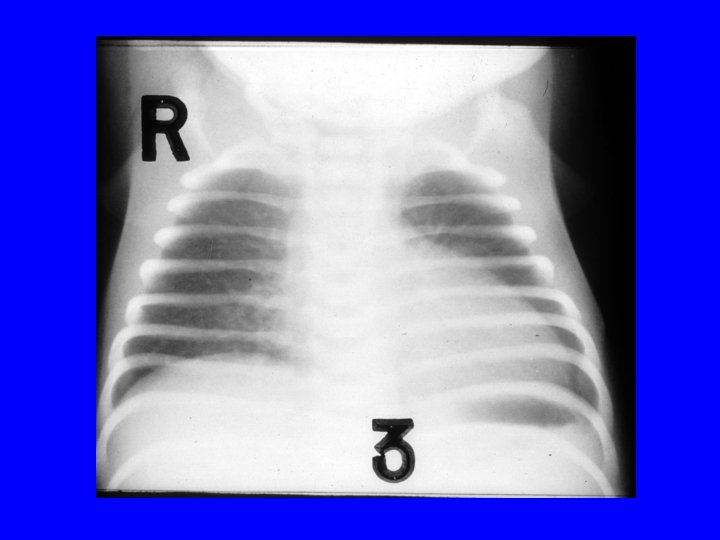

Question 2 • A 28 w GA male infant weighing 1500 g experiences respiratory distress requiring ventilation soon after birth. Ventilator parameters are: SIMV of 40 /min, 22/5 pressures and Fi. O 2 of 0. 8 to maintain a Pa. O 2 of 60 mm Hg. CXR shows. . .

RDS-Surfactant Deficiency • Clinical course: Peak-1 to 3 d and recovery starts with onset of diuresis • Risk Factors: Low GA, male gender , Mat. DM, perinatal depression • RDS in term: SPB def, IDM, Beckwith Weideman syndrome, congenital syphilis • Pathology: Hyaline membrane (cellular debris in fibrinous matrix) • Treatment-surfactant replacement, supportive • Complications: pneumothorax • DD for reticulogranular CXR- GBS pneumonia, PAPVR